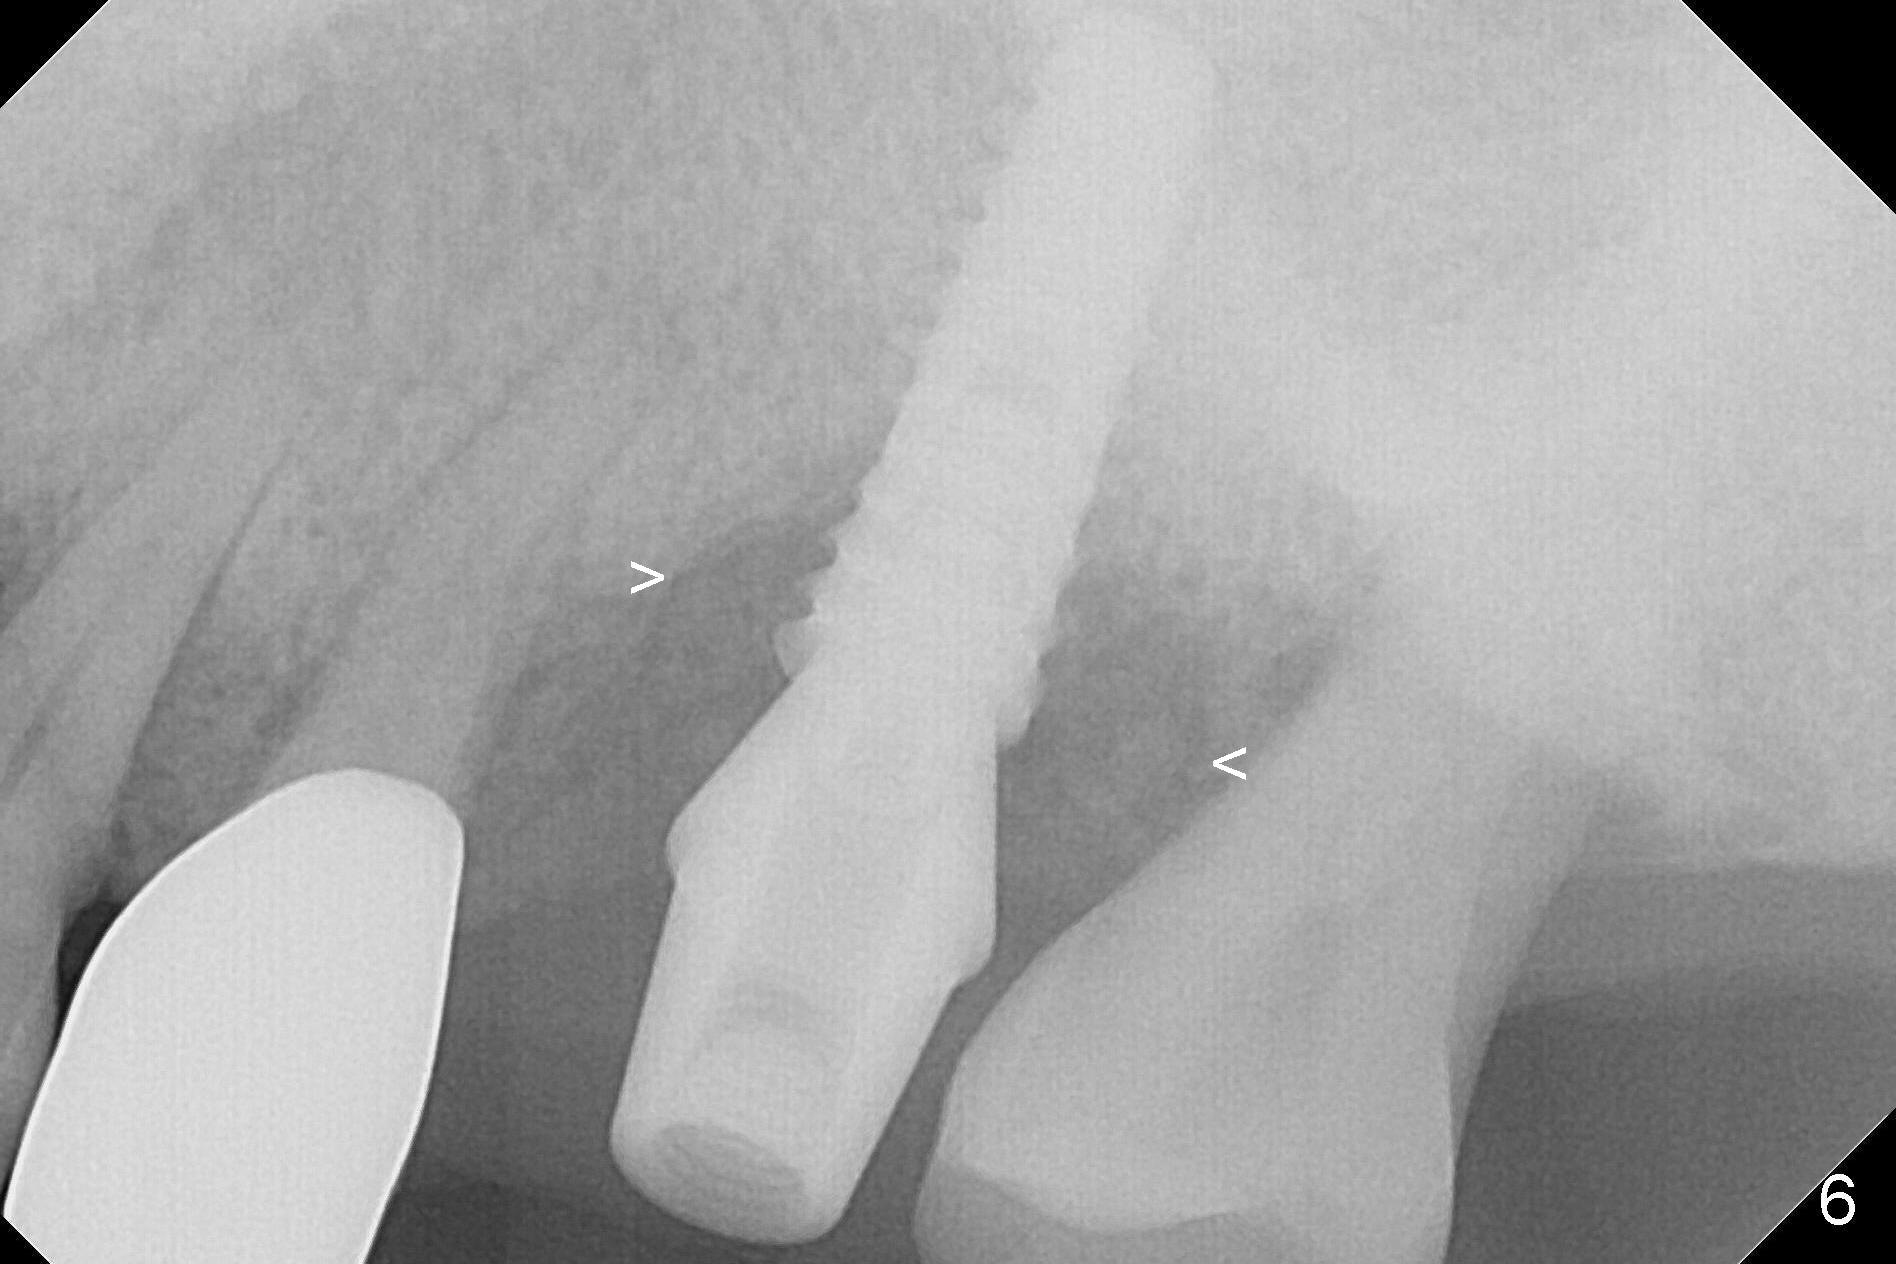

The amount of the bone graft mesial and distal the implant seems to reduce 3 and 4 months postop, respectively (Fig.6,7 arrowheads). When the acrylic is cut off 4 months postop, the bone graft is loose. The gingiva is unhealthy. The abutment and implant are loose. A healing abutment is placed (5x4 mm). The implant is torqued to 35 Ncm 6 months postop with the healing abutment reapplied. The patient will return for follow up nearly 9 months postop. A larger healing abutment will be used if the implant is stable. Two weeks later, use a smaller restorative abutment for easy impression. In fact the implant is unstable with #15 mesial shift due to abnormal occlusion with #17 (Fig.8). Bone density around the implant is low (* in Fig.9 (PA), 10,11 (CT sagittal, coronal sections)). A healing screw is placed for self healing. A 2nd option is to remove the implant (Fig.12), BEB (Fig.13) and place the implant deeper (Fig.14) or larger one (5.5-6.5x13 mm). The 3rd option is to place larger and longer implants (Fig.15 (tapered), 16 (cylindrical)). The implant access has partially closed 14 months postop, but there is a small buccal opening with sanguine exudate. Incision reveals severe bone loss around the implant; the mobile tooth #15 is extracted (Fig.17). After debridement and irrigation with normal saline, Vera Graft (Fig.18 *) and Collagen plug are placed with periodontal dressing.